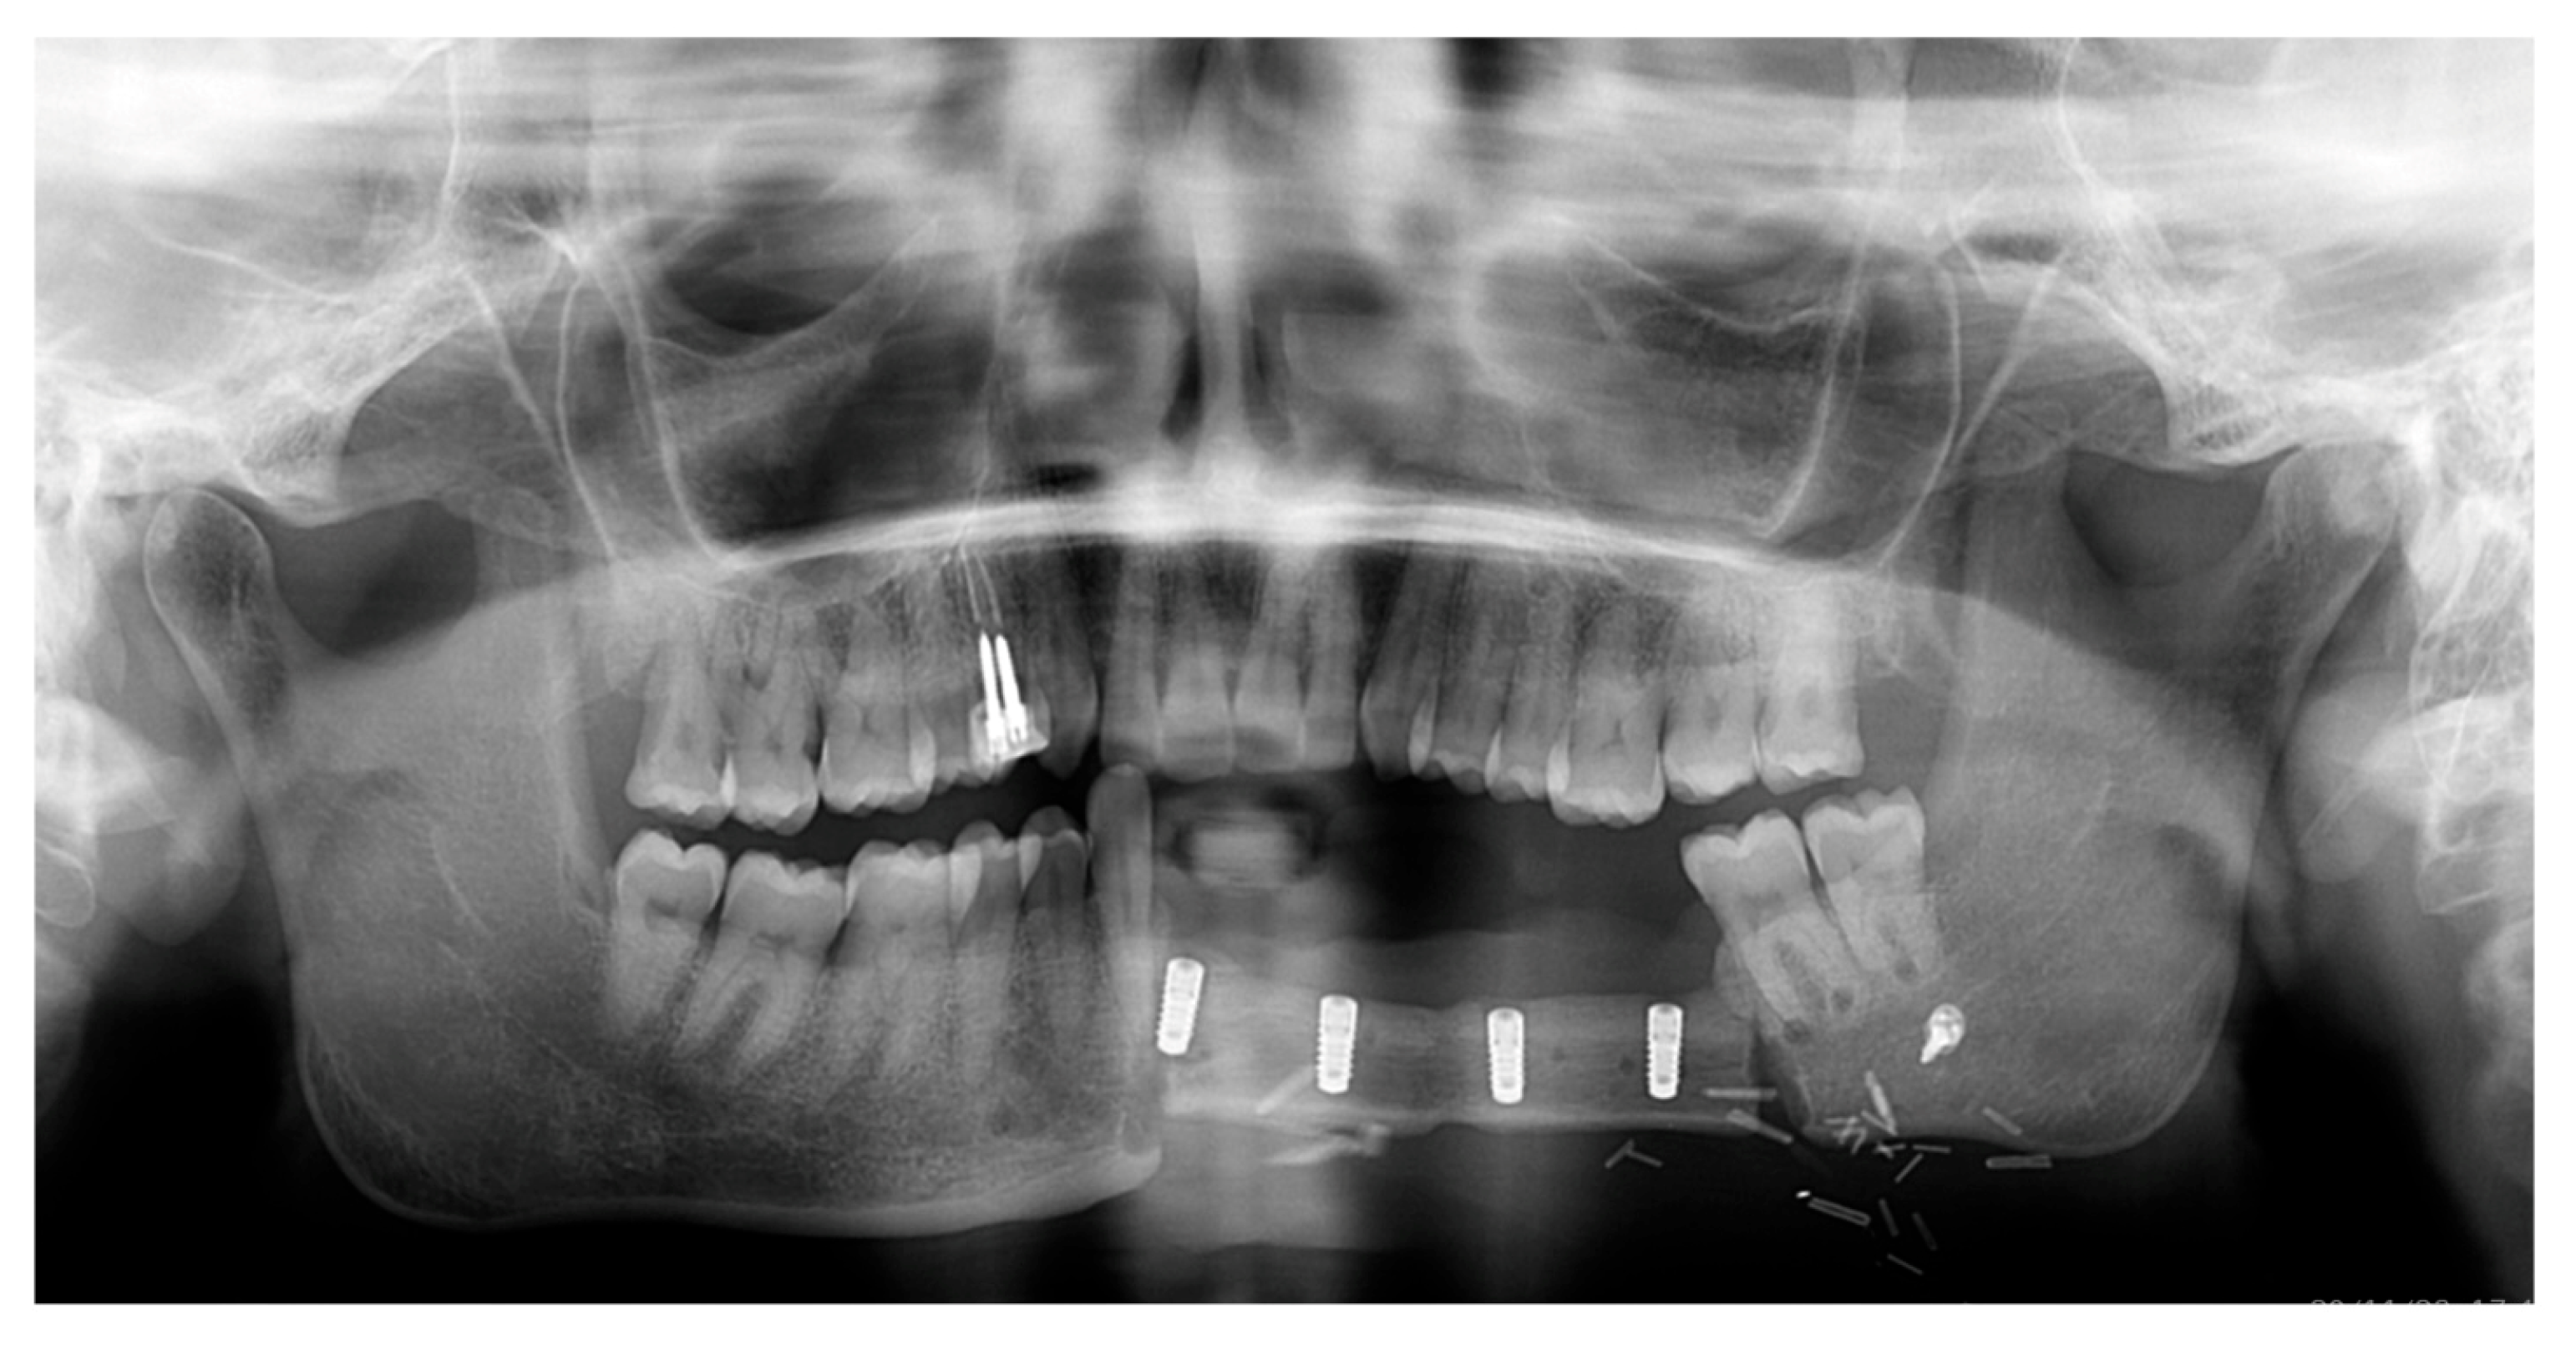

A 44-year-old female patient presented to the Oral Surgery department of the University Hospital of Pisa with a swelling in the left lower jaw, seeking specialist medical advice. The intraoral examination revealed a raised, painless, and tender-at-palpation mass in the buccal vestibular area of the lower left mandible, extending into the labial region, with normal color and the appearance of the surrounding mucosa (Figure 1).

Figure 1. Clinical initial situation in frontal vision (A), and close-up view of the lesion (B).